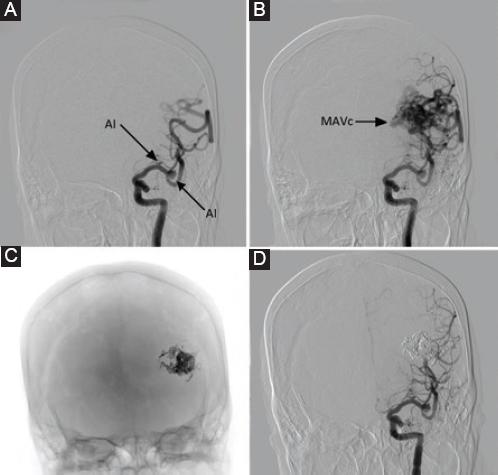

Mujer de 51 años, sin antecedentes médicos ni quirúrgicos, con historia de cefalea de 30 años de evolución que se presentaba de tres a cinco veces por mes, de tipo holocraneana, pulsátil, de moderada intensidad, que cedía con la ingesta de antiinflamatorios no esteroideos, sin alteraciones neurológicas asociadas. Incidentalmente, por el estudio de una masa en el cuello que se protocolizó con estudios de imagen, se evidenció un cortocircuito arteriovenoso parietoccipital medial izquierdo, por lo que es referida al servicio de neurocirugía, donde se le realiza angiografía diagnóstica y se encuentra una malformación arteriovenosa de 33 × 26 × 32 mm en la región parietooccipital izquierda, que recibía suministro sanguíneo a través de las arterias cerebral media izquierda y cerebral posterior homolateral, con drenaje venoso superficial hacia el seno sagital superior y el seno transverso, clasificándose como de grado III en la escala de Spetzler-Martin, con aneurismas proximales de 3.1 × 2 × 3.3 mm en el segmento M1 y de 5.7 × 6.2 × 7 mm en la bifurcación de la arteria cerebral media izquierda. Se plantea como manejo inicial la embolización de los aneurismas proximales con material cohesivo, pero durante la intervención endovascular se observa una compresión de la arteria temporal posterior, por lo cual se decide retirar el material cohesivo y dar por concluido el procedimiento de manera incompleta. Posteriormente se plantea embolizar la malformación arteriovenosa a través de la arteria occipital izquierda, logrando una embolización del 90% (Fig. 1), y en un segundo tiempo quirúrgico se realiza el clipaje del aneurisma de mayor tamaño, a través de un abordaje pterional izquierdo, monitorizando con Doppler transcraneal las velocidades de flujo sanguíneo durante todo el procedimiento (Fig. 2). Finalmente se concluye sin complicaciones y la evolución en su recuperación es adecuada. A los 6 meses se realiza una craneotomía para la resección completa de las malformaciones arteriovenosas cerebrales, que concluye sin complicaciones, con sangrado mínimo y adecuada recuperación neurológica (Fig. 3).

Figura 1 A: angiografía con sustracción digital en proyección anteroposterior en la que se observa un aneurisma pequeño del segmento M1 y un aneurisma mediano de la bifurcación de la arteria cerebral media izquierda. B: malformación arteriovenosa parietooccipital izquierda de 23 × 26 × 22 mm con drenaje profundo, Spetzler-Martin II. C: molde de ónix de la malformación arteriovenosa embolizada. D: control angiográfico tras la embolización.